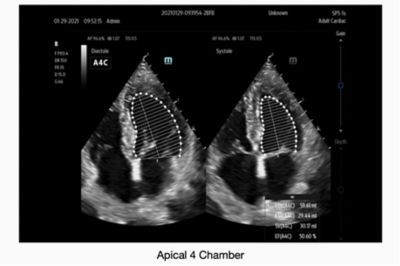

Source: www.mindray.com TE7 Point of Care Ultrasound Systems Mindray , We believe that a multi-layered approach is the best practice in keeping patient information confidential. A Mindray TE7 Max ultrasound is shown being used in and exam room by doctors during a diagnostic medical imaging medical procedure

Source: www.ultrasoundportables.com Mindray TE7 Max Portable Ultrasound Machines for Sale UDS , A Mindray TE7 Max ultrasound is shown being used in and exam room by doctors during a diagnostic medical imaging medical procedure TE5 | TE7 | TE7 Max Diagnostic Ultrasound System (Basic) Operator's Manual